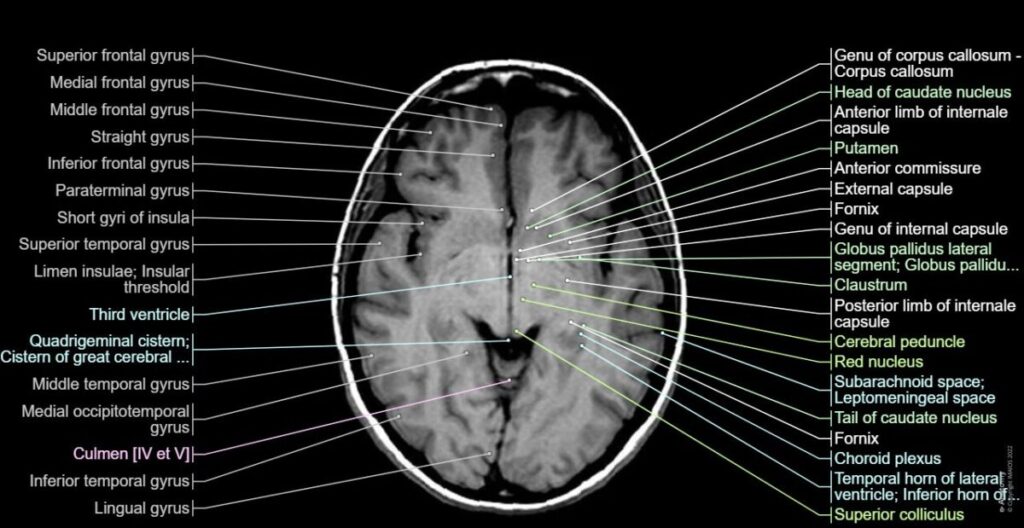

④ MRI(磁気共鳴画像)1970年代後半

磁場と電磁波で水素原子を測定。

特徴

意義

脳構造を詳細に観察可能になった。